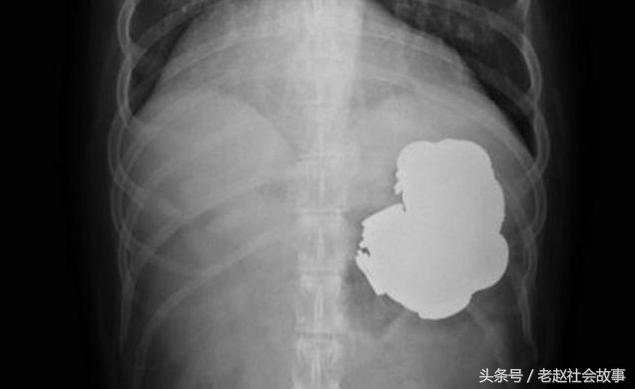

Vì vậy, các bác sĩ lập tức giúp anh khám nội soi và chụp X-quang. Kết quả kiểm tra cho thấy trong dạ dày anh có những vật chất lạ.

Đó là những đồ vật bằng kim loại, trong đó có 140 đồng tiền, 150 cây đinh, bu lông cũng như một loạt các hạt sắt nhỏ. Các bác sĩ cho biết, nếu không được điều trị kịp thời kim loại trong bụng sẽ làm thủng dạ dày, có thể dẫn đến tử vong.

Đồng tiền xu, đinh, bu lông được lấy ra từ dạ dày của anh Singh.